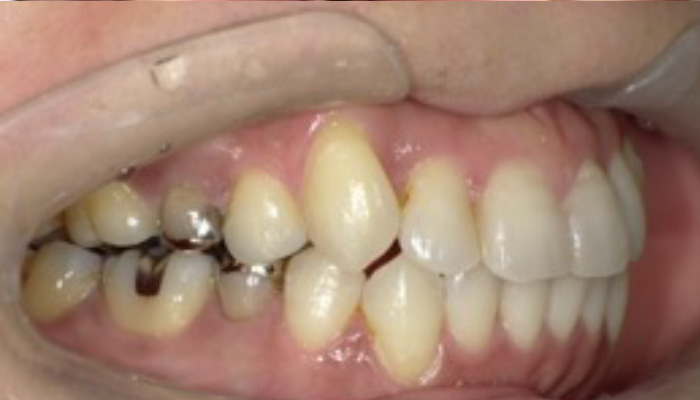

初診時の口腔内写真